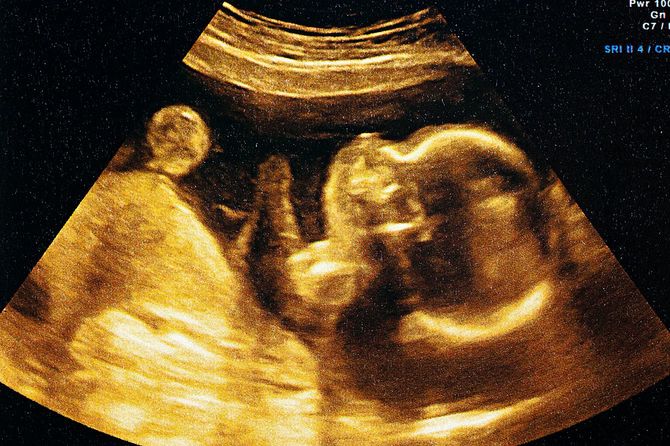

夫の不倫が発覚した2カ月後、なんと2人目の妊娠が判明。